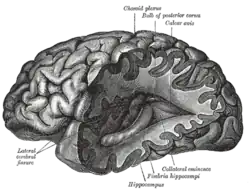

Изучение человеческого мозга является междисциплинарной наукой и включает в себя много уровней изучения, от молекулярного до клеточного уровня (отдельные нейроны), от уровня относительно небольших объединений нейронов до уровня больших систем, таких как кора головного мозга или мозжечок, а также на самом высоком уровне — уровне нервной системы в целом.

Параллельно с этим исследованием, работая с поврежденными мозгами пациентов, Поль Брока предполагал, что определённые области мозга ответственны за определённые функции. В то время выводы Брока рассматривались как подтверждение теории Франца Йозефа Галля о том, что речь локализована и что определённые психологические функции локализованы в определённых областях коры головного мозга[8][9]. Эту гипотезу подтверждали наблюдения эпилептических пациентов, проведенные Джоном Хьюлингсом Джексоном, который правильно вывел организацию двигательной коры, наблюдая за прогрессированием судорог через тело. Карл Вернике далее развил теорию специализации конкретных структур мозга в понимании и производстве речи. Современные исследования с помощью методов нейровизуализации по-прежнему используют анатомические определения цитоархитектонических полей Бродмана (ссылаясь на изучение структуры клетки) с этой эпохи, продолжая показывать, что отдельные области коры активируются при выполнении конкретных задач[10].

Нейрохирург Уайлдер Пенфилд, занимавшийся хирургическим лечением эпилепсии, к середине XX века составил карту динамической локализации функций коры головного мозга. Во множество учебников вошла его схема, где изображена представимость различных органов человека в его головном мозгу[12][13][14][15][16].